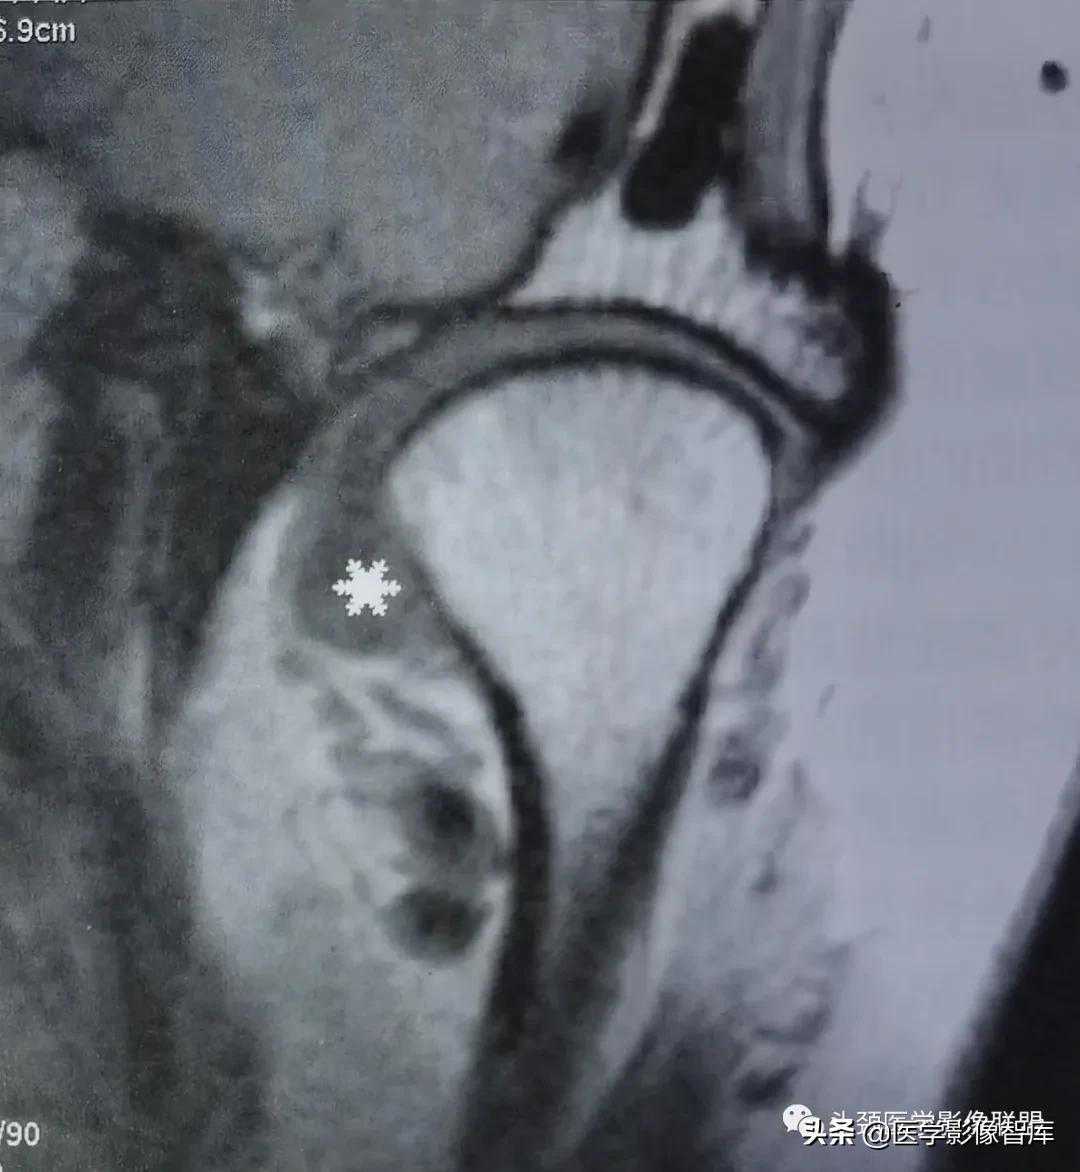

图2不可复性关节盘前移

A.矢状面闭口PDWI示关节盘后带(黑星)位于髁突前方;B.矢状面开口T2WI示:关节盘随下颌髁突前移,仍位于其前方。关节盘无变形,盘后附着相对拉长。关节上腔内有中量积液。下颌髁突活动度小。

不可复性盘前移位的主要临床表现为髁突活动受限。它是指闭口位时,关节盘位于下颌髁突横嵴顶的前方;张口时,随着下颌髁突向前移动,撞击关节盘后带,迫使其进一步向前移动。关节盘不能向后反跳越过髁突,因此也就不能恢复正常的盘一髁关系。不可复性盘前移位的MRI表现特点为:矢状面闭口位上(图2A),低信号的关节盘明显位于髁突横嵴顶12点位的前方,关节盘后双板区被明显牵拉变长,并移位于髁突横嵴顶12点位的前方;矢状面张口位上(图2B),关节盘双板区因拉伸而变直,关节盘仍位于下颌髁突的前方,不能恢复正常的盘一髁关系。

图3不可复性关节盘前移伴盘变形

A.矢状面闭口PDWI示:关节盘后带(黑星)位于下颌髁突前方;B.矢状面开口T2WI示:关节盘随下颌髁突前移,仍位于其前方。开闭口位上均见关节盘呈变形改变:关节盘前带弯曲折迭,关节盘后带相对增厚。下颌髁突活动度小。

关节盘变形主要出现在不可复性盘移位中。变形的关节盘可以出现在闭口位上,也可以出现在张口之后。张口时的关节盘变形明显多见,主要是关节盘受向前运动之下颌髁突挤压所致。MRI上,变形的关节盘失去正常时双凹形或蝶结状轮廓,可以呈多样性表现,如关节盘前带弯曲折迭,关节盘后带增厚,盘后双板区纤维化和伴有盘中带缩短的盘后带增大等。由于下颌髁突在张口前移时受到前方关节盘的阻挡,故在MRI上常能显示下颌髁突活动受限。此时,下颌髁突之大部仍位于颞骨关节窝内,不能到达关节结节的下方或前下方(图3)。